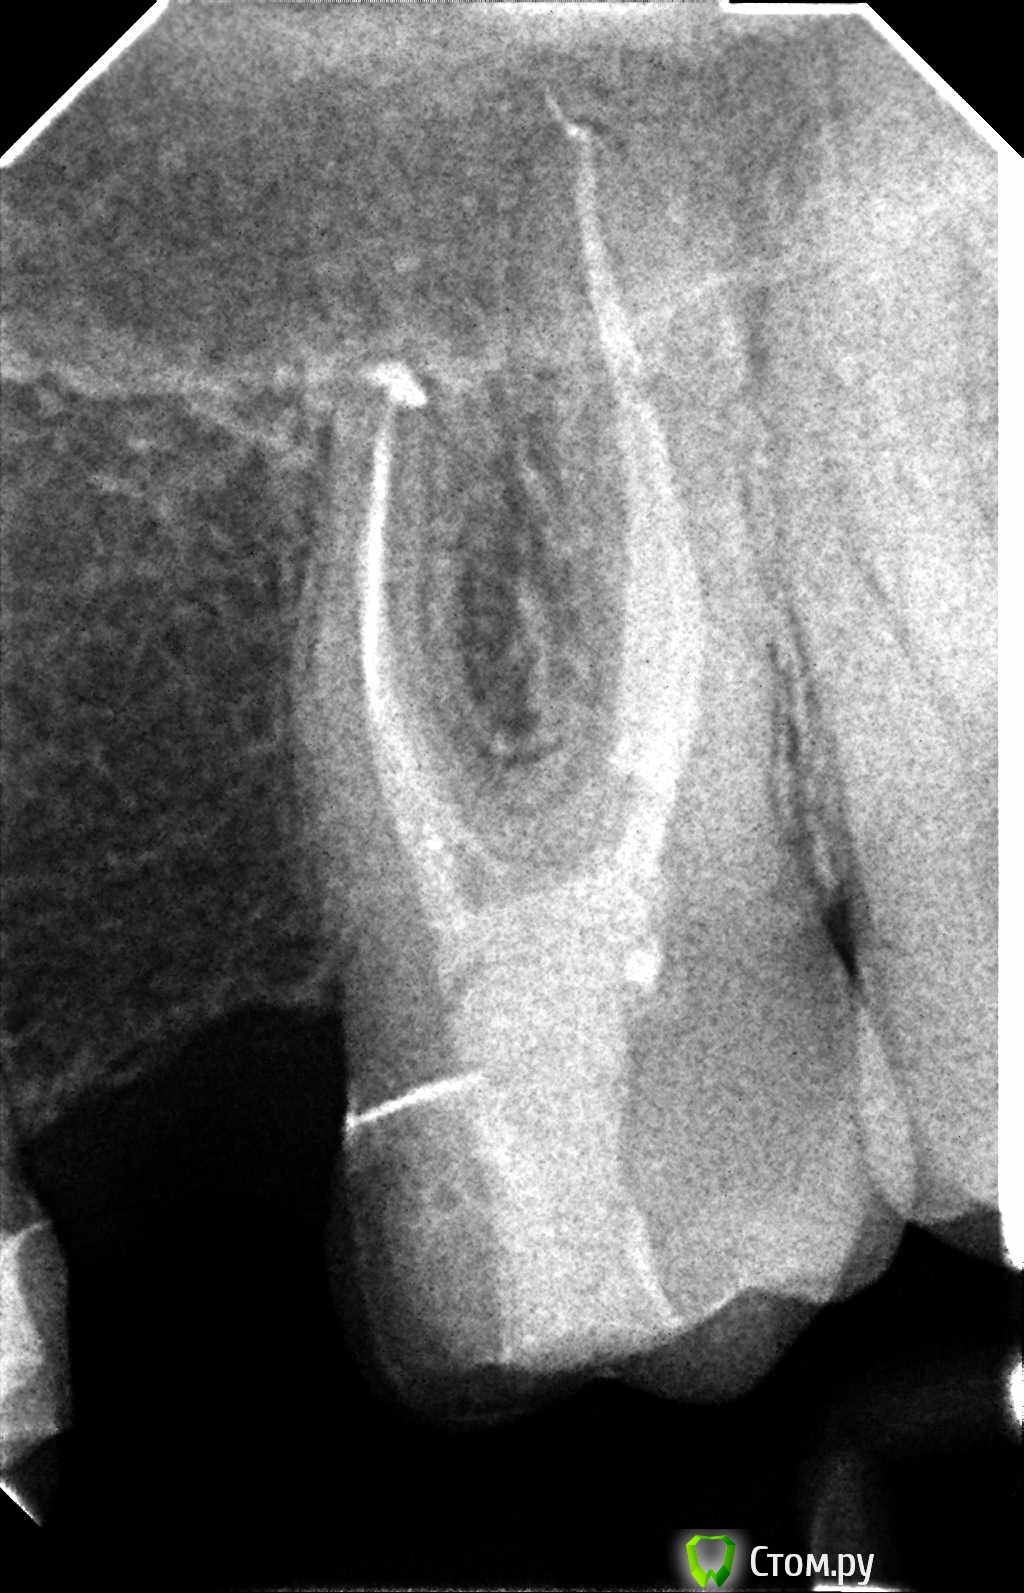

Hans85 Опубликовано 9 января, 2014 Автор Поделиться Опубликовано 9 января, 2014 (изменено) Так теперь попробуем выстроить нормальную логическую цепочку.Кейс из разряда сам сломал сам доставай-благо канал относительно прямой,времени удаление фрагмента заняло 15-20 минут.Сломал кстати протейпер S2 Изменено 9 января, 2014 пользователем Hans85 8 Ссылка на комментарий

Hans85 Опубликовано 9 января, 2014 Автор Поделиться Опубликовано 9 января, 2014 Hans85, как извлекли инструмент? Судя по апексу - был риск протолкнуть отломок за апекс. Клевый кейс! Сделал минимально пространство в области торца инструмента 15 U-File чуть расшатал и с водой озвучивал рассчитывая на гидроудар. Ссылка на комментарий